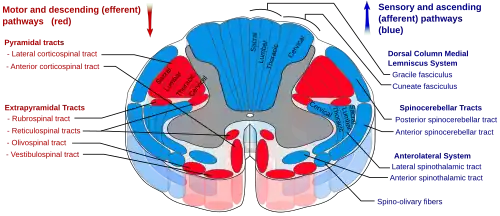

Спиноталамический путь

Восходящие нервные пути, соединяющие спинной мозг с таламусом, образуют спиноталамический путь, или спиноталамический тракт. В нём от спинного мозга к таламусу передаётся сенсорная информация о болевых, температурных и тактильных ощущениях, а также об ощущении зуда[14]. Спиноталамический путь подразделяется на две части: боковой, или латеральный, или дорсальный, спиноталамический путь[15], который передаёт информацию о болевых и температурных ощущениях, и передний, или вентральный, спиноталамический путь[16], который передаёт ощущения грубого прикосновения или сдавливания, надавливания[8].

В свою очередь, в боковом спиноталамическом пути выделяют эволюционно более молодой неоспиноталамический путь и более древний палеоспиноталамический путь. Первый состоит из большого количества тонких нервных волокон, которые быстро проводят болевые ощущения, а второй содержит меньшее количество более толстых и более медленно проводящих нервных волокон. Быстро проводящий неоспиноталамический путь играет большую роль в передаче в мозг хорошо локализованного ощущения острой боли непосредственно или вскоре после травмы, повреждения тканей, и в принятии организмом защитных мер, таких, например, как отдёргивание руки от горячего предмета. Более медленно проводящий палеоспиноталамический путь передаёт менее локализованную, более разлитую, тупую, давящую или сжимающую, реже жгучую или сверлящую хроническую боль, и играет большую роль в патогенезе различных хронических болевых синдромов[17][18].